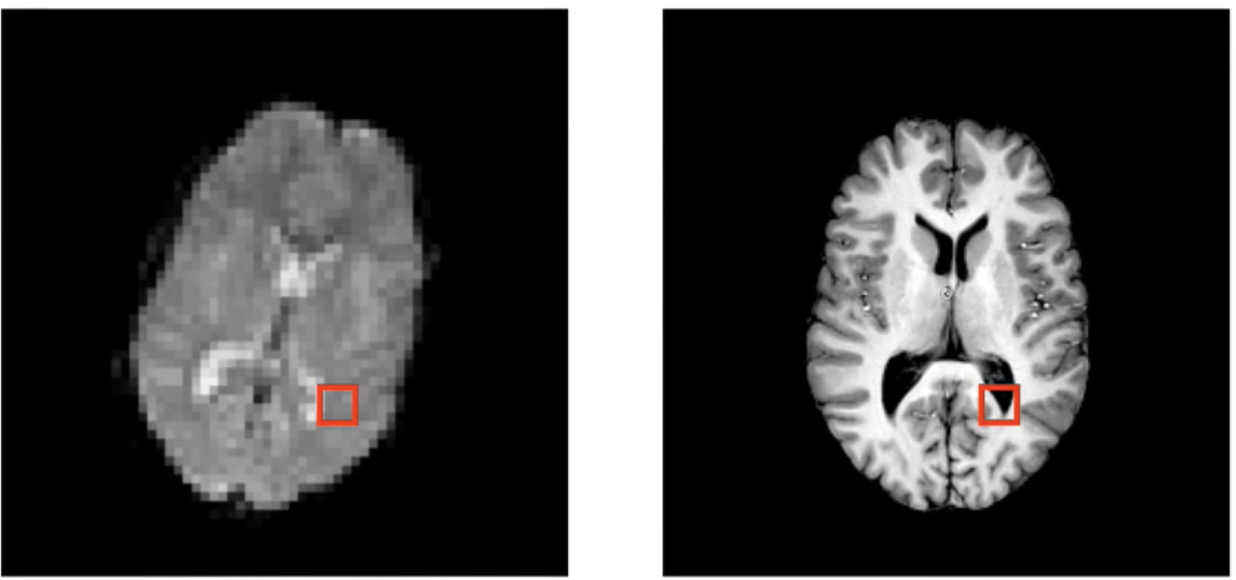

在这两张图片上,很容易看出它们没有对齐,左边相对右边倾斜,虽然我们人类视觉系统还是能把对应的解剖关系连系在一起,但是我们使用计算机分析时确不能够

因此,我们希望相同的解剖结构对齐,用坐标表示的话,希望他们在相同的坐标上。如下图

对齐这些解剖结构的过程就叫做配准(register)